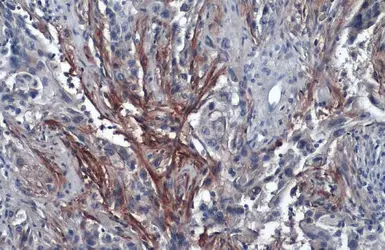

Anti-Carbonic Anhydrase IX antibody [GT12] used in IHC (Paraffin sections) (IHC-P). GTX70020

GTX70020 IHC-P Image

The data was published in the journal PLoS One in 2015. PMID: 25738958